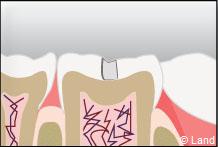

Les traitements possibles pour les stades de la carie où seuls l’émail et la dentine sont touchés peuvent se faire avec de l’amalgame qui est un matériau indiqué dans la restauration des petites et moyennes cavités.